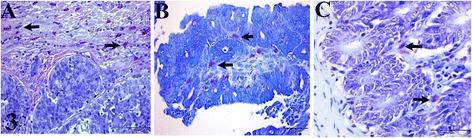

Ki67 index, tumor associated macrophages (TAMs) and mast cells (MCs) are associated with malignancies in animal and human neoplasms including colorectal carcinomas (CRC). This has not been assessed in canine CRC. Given similar genetic abnormalities between human and canine CRC, we assessed Ki-67 and mitotic indices, TAMs and MC count (MCC) in canine CRC (n = 17). TAMs and MCC were compared with those in adenomas (n = 13) and control (n = 9).

RESULTS

Ki-67 index in CRC (17.13 ± 11.50) was strongly correlated (r = 0.98, p < 0.05) with mitotic index (3.52 ± 1.80). MCC was higher (p < 0.05) in CRC (6.30 ± 3.98) than in adenomas (0.78 ± 0.77) and control (0.35 ± 0.33). The results suggest that Ki-67 index and MCC are associated with malignancy in canine CRC. Higher average TAMs were counted in adenomas (21.30 ± 20.70) and in CRC (11.00 ± 9.82) than in the control (7.69 ± 7.26), although the differences were not significant (p > 0.05).

CONCLUSION

Ki-67 index, TAMs and MCC in canine CRC were recorded for the first time in this study. Ki-67 index and MCC are associated with malignancy in canine CRC. Quantitative assessment of MCs and Ki-67 coupled with mitotic index and other clinical parameters may help in evaluating malignancy in canine CRC. TAMs likely play a role in the development of canine colorectal tumors. Further studies to determine the clinical significance of these parameters for prognostic, chemo-preventive and chemotherapeutic purposes in canine colorectal tumors are recommended.